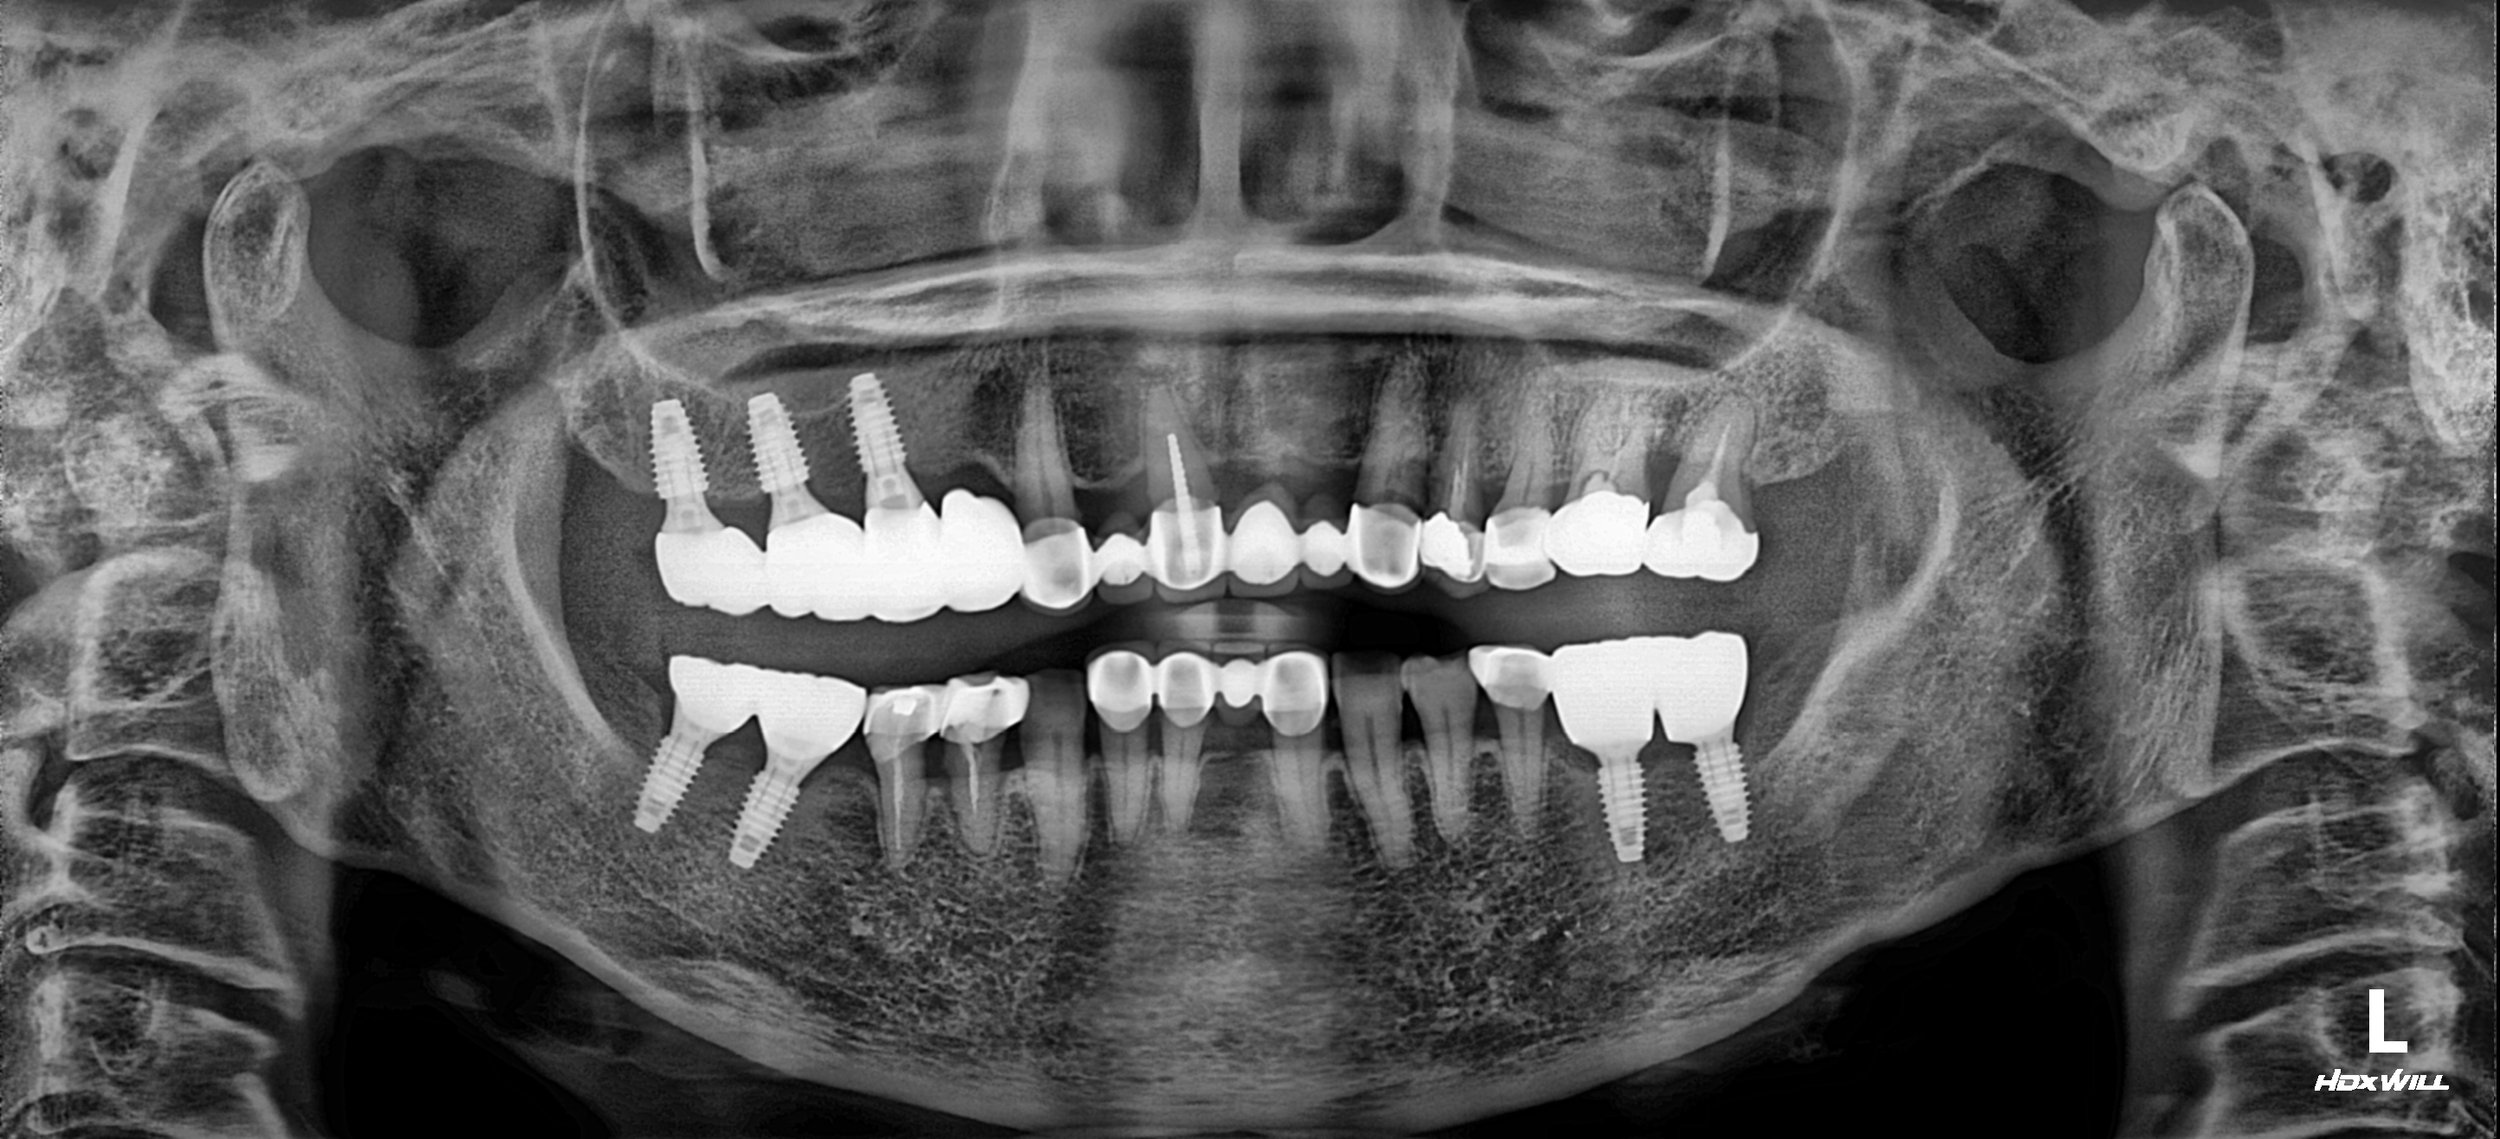

OPG - BEFORE

• Restoration of posterior occlusal height through bilateral prosthetic elevation

• Anterior–inferior repositioning of the mandible to improve jaw stability

• Relief of temporomandibular joint symptoms through occlusal correction

• Creation of adequate prosthetic space for posterior implant restorations

Posterior occlusal vertical dimension was selectively increased to guide

mandibular repositioning and re-establish functional occlusion.